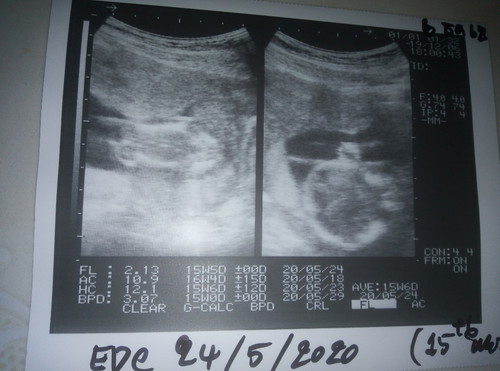

สวัสดีค่ะ เราเป็นคนที่ประจำเดือนมาไม่ปกติ 8เดือนมาที 9เดือนมาที เป็นมาแบบนี้แต่ไหนแต่ไรก็ไม่ได้ไปหาหมอ ช่วงเดือน กย เรามีอาการอยากกินผลไม้แช่อิ่ม พอตอนดึกๆมีอากอ้วก แล้วก็เป็นมาถึง พย ก่อนหน้าได้ไปพบหมอแล้วก็บอกว่าเป็นกระเพาะอาหารอักเสบ จึงได้กลับมาบ้านช่วงต้นเดือน พย มาหาหมอ หมอก็บอกว่าเป็นกระเพาะอาการก็ไม่ดีขึ้น อ้วกทุกวัน แต่เริ่มกินอาหารได้ ช่วงเดือน ตค ได้ไปซื้อที่ตรวจครรภ์มาตรวจขึ้น1ขีด จึงคิดว่าไม่ไม่ท้อง พอกลับมาบ้านช่วงเดือน ธค จังไปนวดหลังเพราะปวดหลังมากไม่หาย คนนวดจึงนวดหลังให้แล้วเขาว่าจะกดท้อง พอหันท้องมาเขาเลยทักว่าท้องนะนิ จึงได้ไปซื้อที่ตรวจครรภ์มาตรวจ ขึ้น2ขีด วันต่อมาจึงไป รพ อีกครั้ง พบว่าท้อง หมอจึงนัดฝากครรภ์ แต่พอไป รพ วันรุ่งขึ้นเป็นวันศุกร์คนในห้องส่งเสริมบอกว่ามาทำไมวันนี้ก็เลยบอกว่าหมอนัด ให้มาใหม่วันหลัง เราจึงใจร้อนไปคลินิคซาวดู คุณหมอบอกว่าได้ 15สัปดาห์แล้ว จึงนัดฝากครรภ์วันพุธนี้ มีใครไม่ทราบไหมคะว่าตัวเองท้อง ถ้าไม่ไปนวดก็ไมรู้จริงๆค่ะว่าท้อง